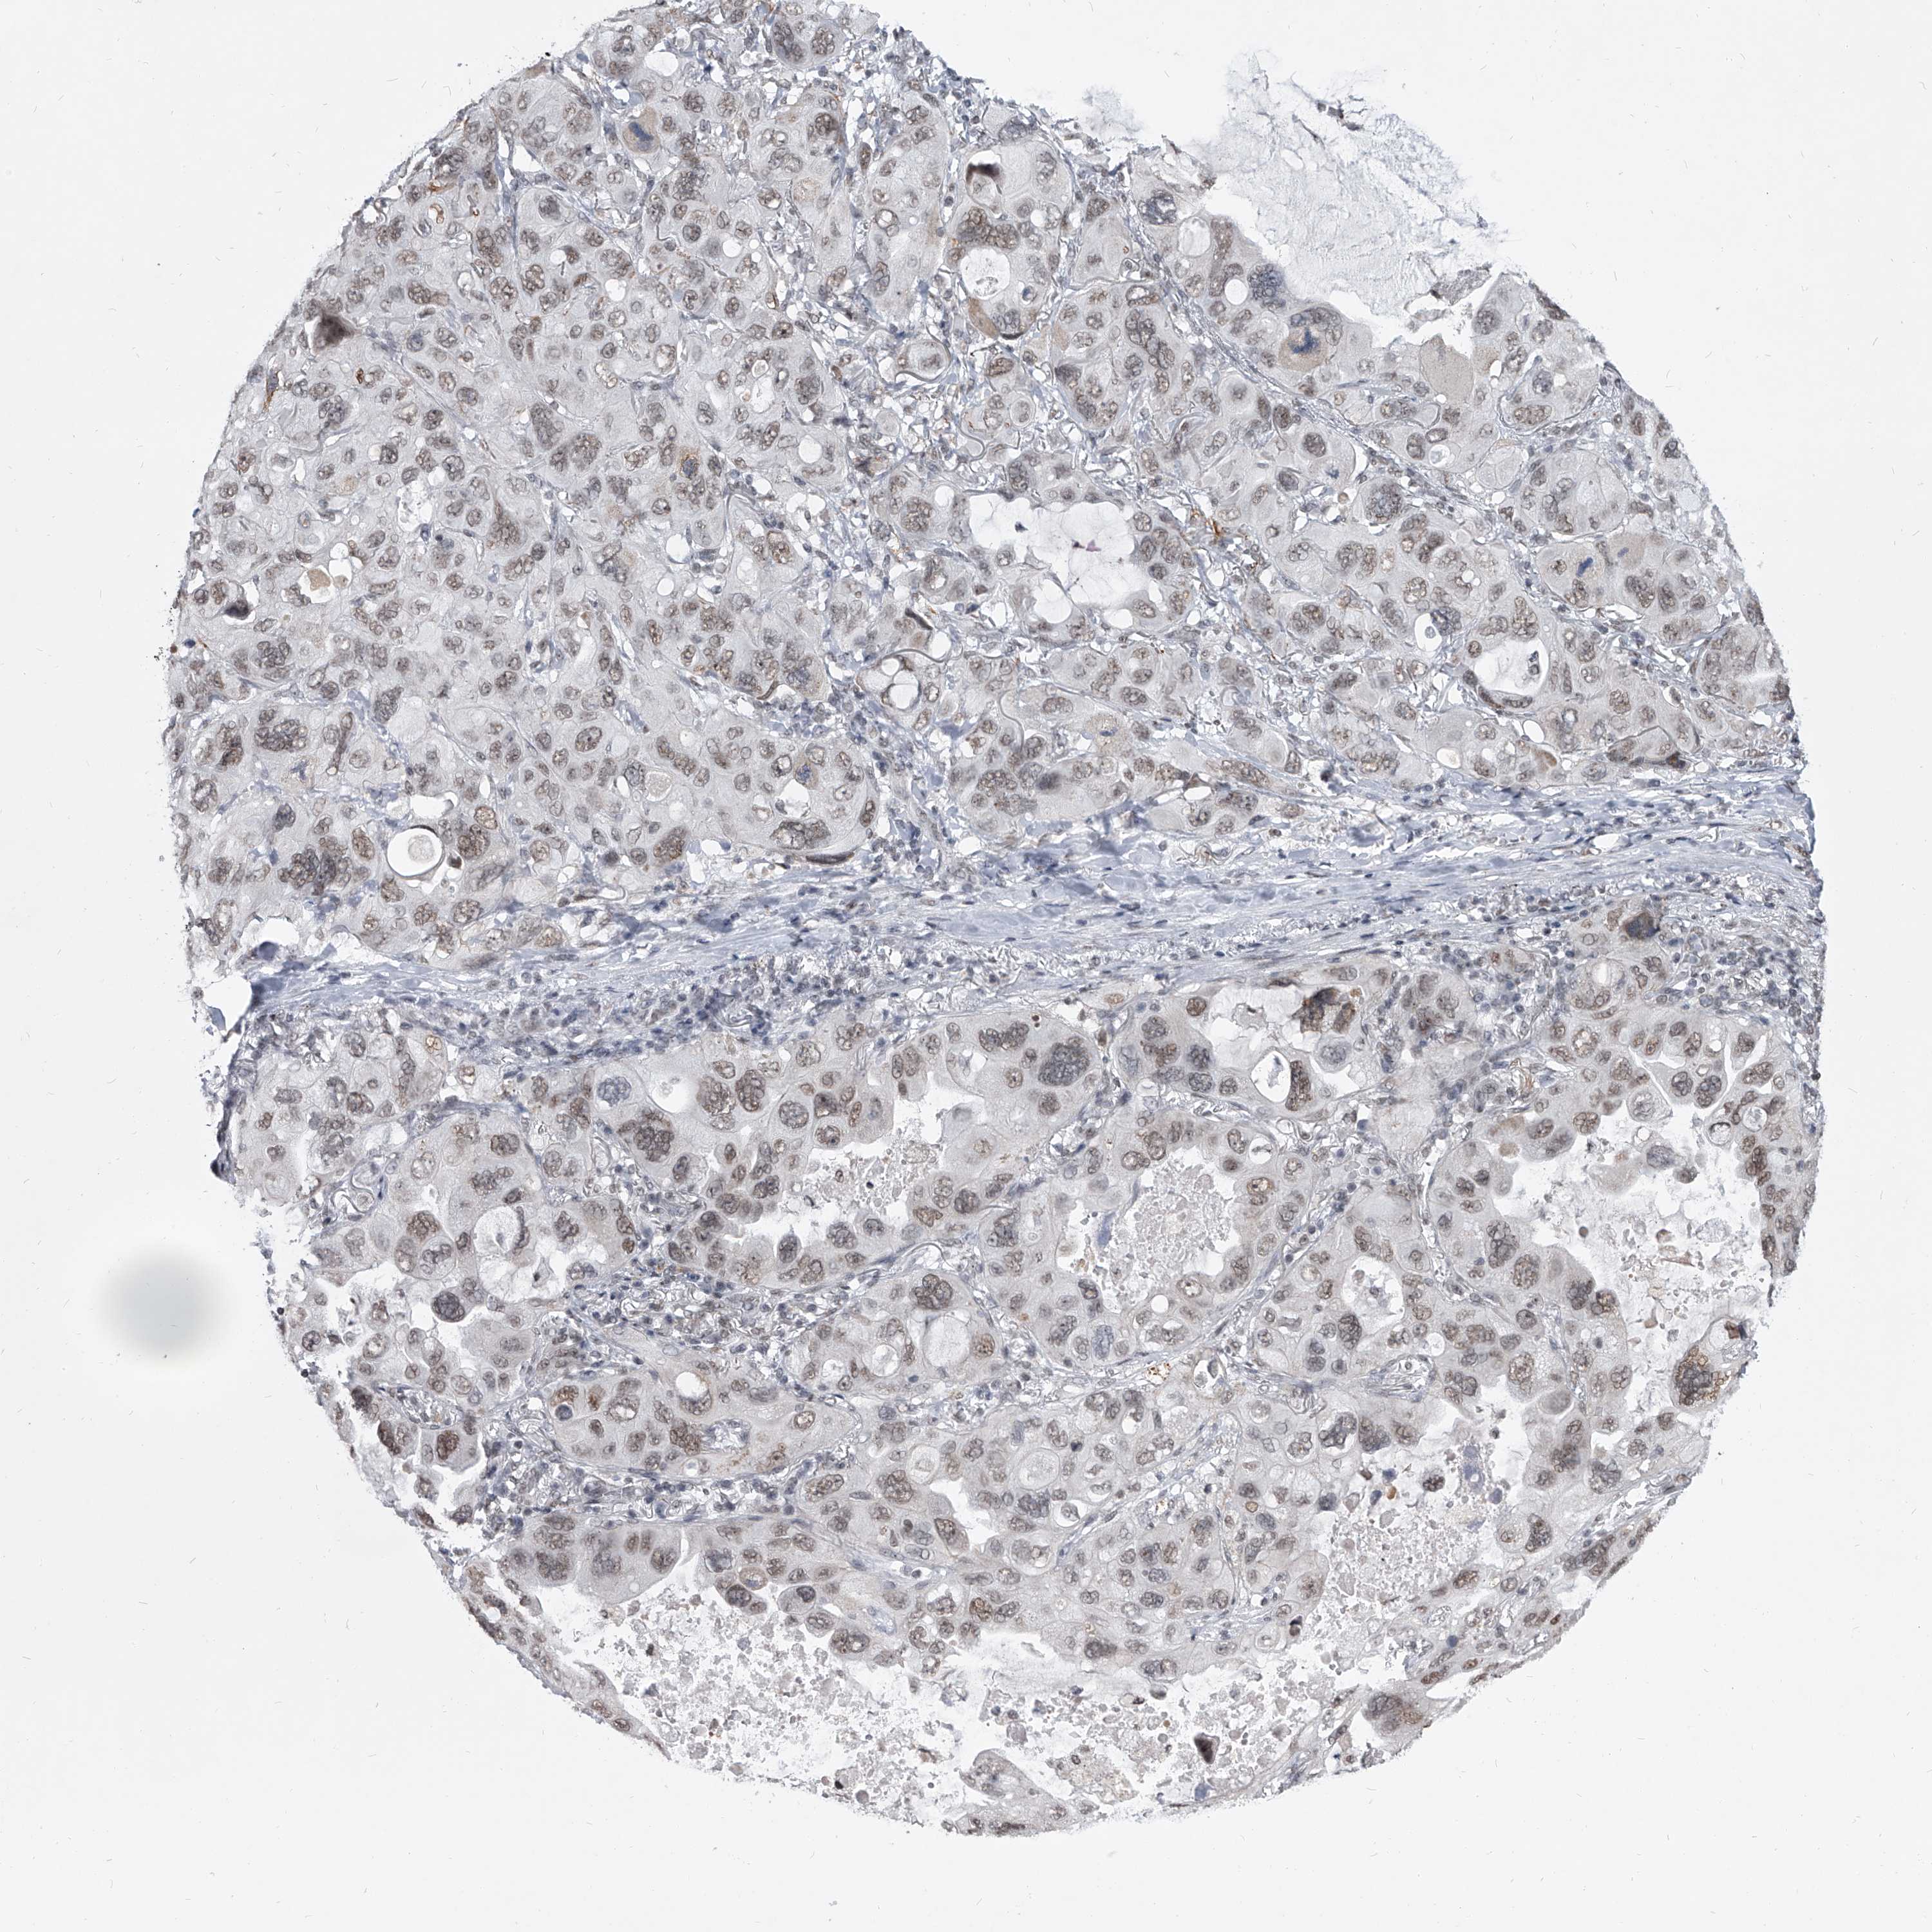

CANCER LUNG CANCER Show tissue menu

LUAD TCGA LUAD VALIDATION LUSC TCGA LUSC VALIDATION PROTEIN LUAD CPTAC PROTEIN LUSC CPTAC PROTEIN EXPRESSION

ANTIBODIES

AND

VALIDATION